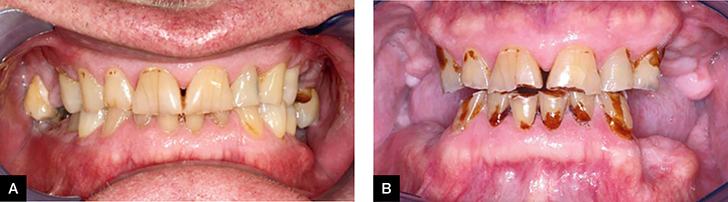

Xerostomia Caries

Dry mouth - Xerostomia and Tooth Decay | Lake Loon Family Dentistry Caries - Dental Disorders - Merck Manuals Professional Edition Cervical Caries - Treatment Options Based Upon Etiology of the Lesion | October 2005 | Inside Dentistry Xerostomia Caries